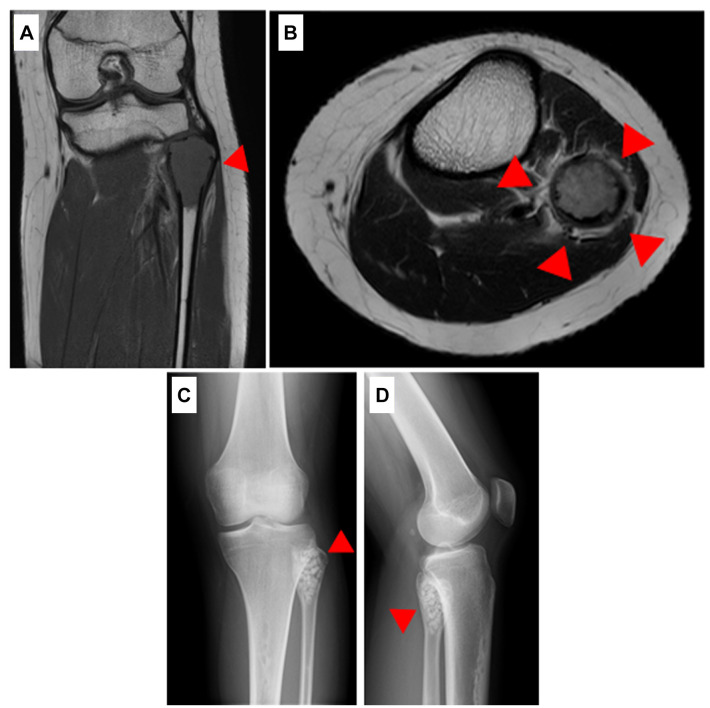

Case report: A 15-year-old female presented to a primary care physician with pain in the lateral aspect of the left knee and was referred to our department with a suspected bone tumor owing to radiographic findings of osteolysis of the proximal fibula. Computed tomography indicated osteolysis of the proximal fibula, and the bone cortex was thin and partially irregular. Magnetic resonance imaging indicated a mass in the same area, with hyperintense changes in both T1- and T2-weighted images. No biopsy was performed; however, bone tumor curettage and artificial bone grafting were performed. The final pathological examination indicated osteoclastic, multinucleated giant cells. No malignant findings were observed, and the patient was diagnosed with GCTB. No recurrence was observed one year after surgery.